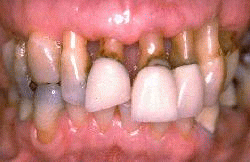

Mujer de 68 años de edad tratada por enfermedad periodontal por medio no quirúrgico (raspado y alisado radicular) seis años antes. El margen  gingival se ha retraído entre 3-5 mm y las profundidades de los surcos al sondaje es de  2 - 3 mm. Ella demuestra una higiene oral excelente y la progresión de la  enfermedad periodontal se ha detenido. Se observa signos de abrasión dental por el cepillado en los incisivos.

Mujer de 68 años de edad  que fue tratada por medio de tratamiento no quirúrgico (raspado y alisado radicular) hace ocho años. El margen  gingival se ha retraído entre 3-5 mm. Las profundidades de los surcos gingivales son 2-3 mm. Ella demuestra una higiene oral excelente y la progresión de enfermedad periodontal se ha detenido. Se observa evidencia de abrasión por el cepilldo dental. a lo largo del margen gingival.